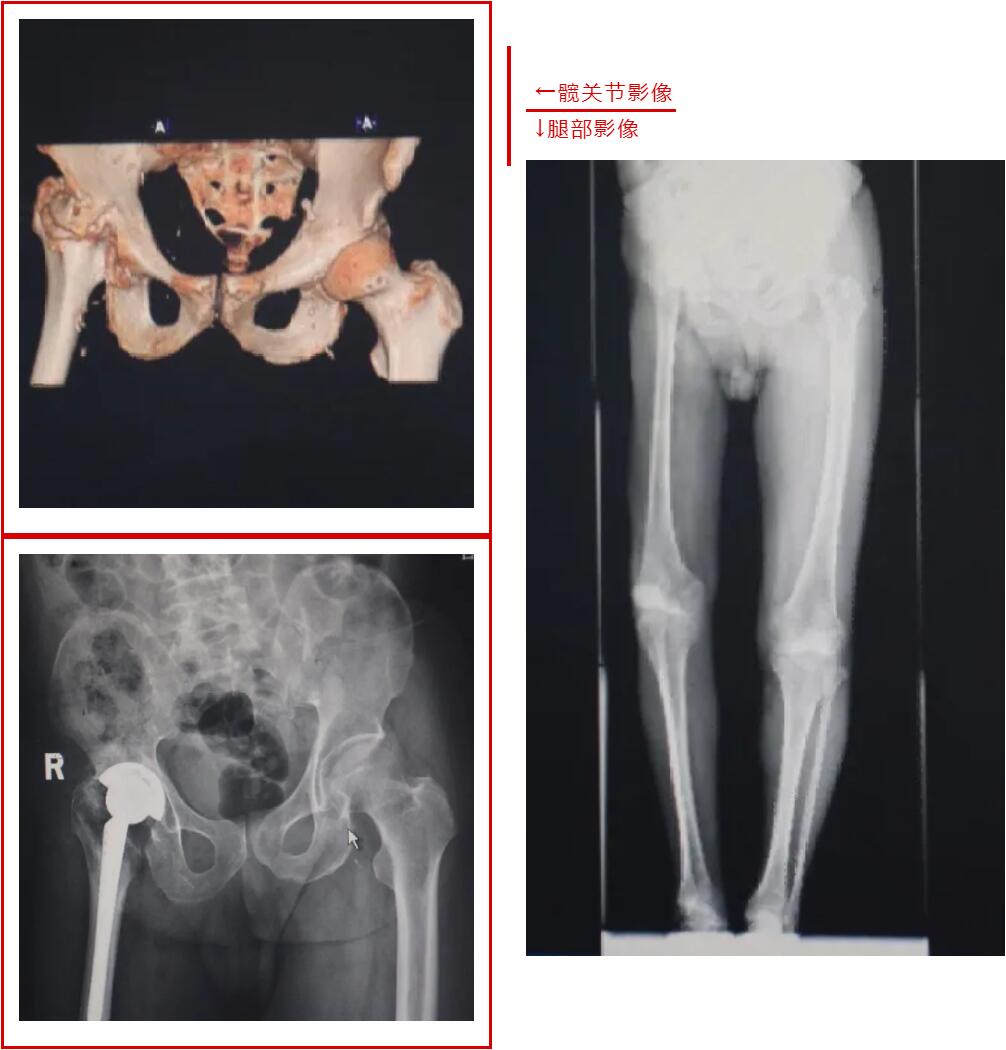

据金大爷和其家属所述,金大爷在三四岁时,曾因腿痛哭闹了好几天,他的母亲以为这不过是小孩子的生长痛,没有放在心上。哭着闹着,金大爷也就习惯了疼痛。等到七八岁时,疼痛加剧,去医院检查,金大爷患的是“化脓性关节炎”,可这依旧没有引起重视,金大爷的母亲给他贴上了一张止痛膏,这种膏药一贴就是六十多年。

随着年龄的增长,金大爷的双腿出现了长短腿的现象,家人却只是觉得是金大爷的命不好,落了个残疾,没往生病方面想。直至今年疼痛实在难忍,金大爷才在家人的陪同下,前往台州市博爱医院关节医学科就诊。

经检查,马大爷的病情比金某更加严重。马大爷今年78岁,他患的化脓性关节炎已有70多年之久,双腿已经严重弯曲,双脚倾斜,不能正常踩地。